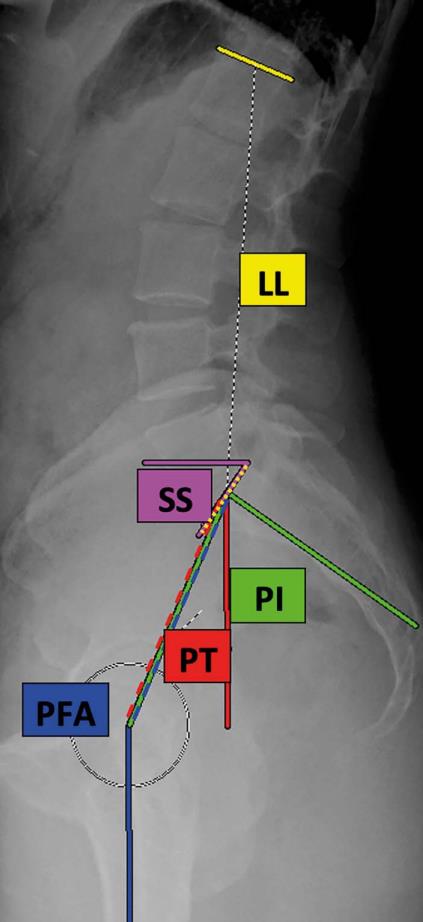

• This was a cross-sectional cohort study of 112 asymptomatic volunteers (age, 47.4 ± 17.7 years; 50.0% female; BMI, 27.3 ± 4.9 kg/m2). All participants underwent lateral spinopelvic radiography in the standing and deep-seated positions to determine maximum hip and lumbar flexion. Lumbar flexion (change in lumbar lordosis, ∆LL), hip flexion (change in pelvic-femoral angle, ∆PFA), and pelvic movement (change in pelvic tilt, ΔPT) were determined. The hip user index, which quantifies the relative contribution of the hip to overall sagittal movement, was calculated as (∆PFA/[∆PFA + ∆LL]) × 100%.